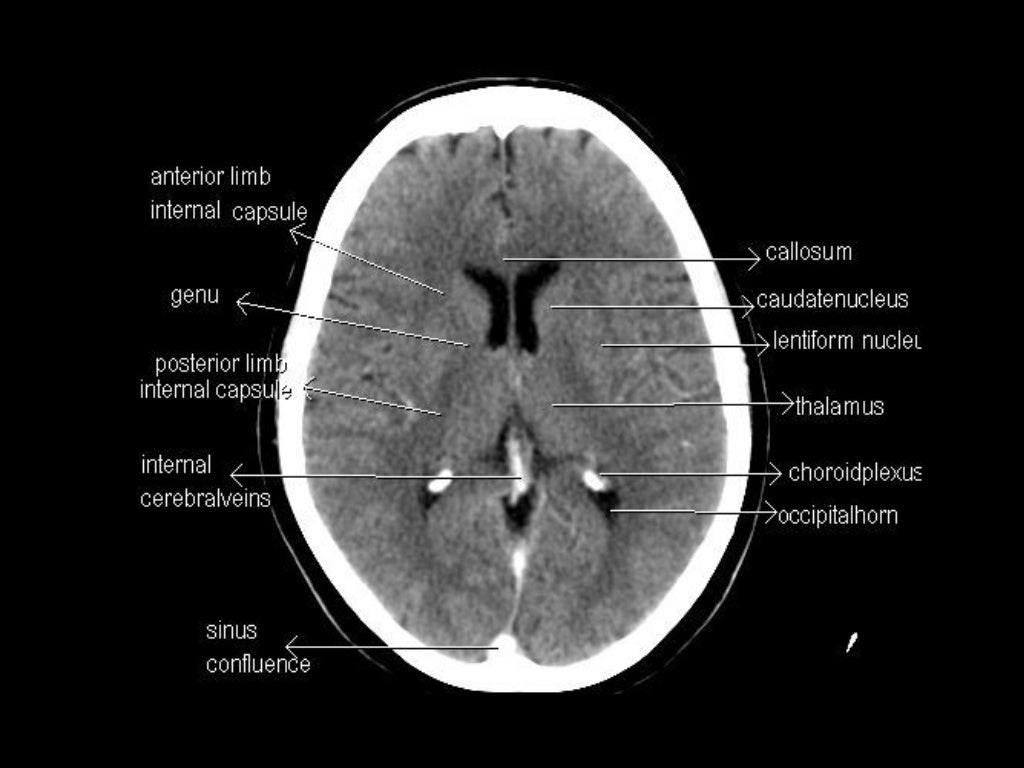

CT Scan Anatomy Overview. CT scans, or Computed Tomography scans, are essential tools in modern medicine. They provide detailed images of the inside of your body and are particularly useful for diagnosing conditions that affect the bone and soft tissues. Understanding CT scan anatomy is crucial for interpreting these images accurately. CT brain - image orientation. Hover on/off image to show/hide findings. Tap on/off image to show/hide findings. Click image to align with top of page. CT brain - image orientation. Roll over the image (tap - mobile devices) to show the annotations; Note the side markers - RIGHT on the viewers LEFT; ANTERIOR brain/head = top of image Fully annotated brain CT - Normal anatomy of the head on a cross-sectional cranial CT Scan (axial, sagittal and coronal): brain, bones of skull, paranasal sinuses, vasculary territories, cranial base. Menu MY ACCOUNT e-Anatomy Human anatomy atlas IMAIOS DICOM Viewer Free DICOM viewer vet-Anatomy Veterinary anatomy atlas Anatomical structures

The data sets were designed to serve as (1) a reference for the study of human anatomy, (2) public-domain data for testing medical imaging algorithms, and (3) a test bed and model for the construction of network-accessible image libraries. The CT data consist of axial CT scans of the entire body taken at 1mm intervals at a pixel resolution The CT scan brain anatomy is a complex and fascinating field of study, offering a detailed look into the structure and function of the human brain. Through the use of computed tomography (CT) scans, medical professionals can visualize the brain's anatomy, identifying various structures, vessels, and pathways. Normal chest x ray. Radiological anatomy is where your human anatomy knowledge meets clinical practice. It gathers several non-invasive methods for visualizing the inner body structures. The most frequently used imaging modalities are radiography (X-ray), computed tomography (CT) and magnetic resonance imaging (MRI).X-ray and CT require the use of ionizing radiation while MRI uses a magnetic